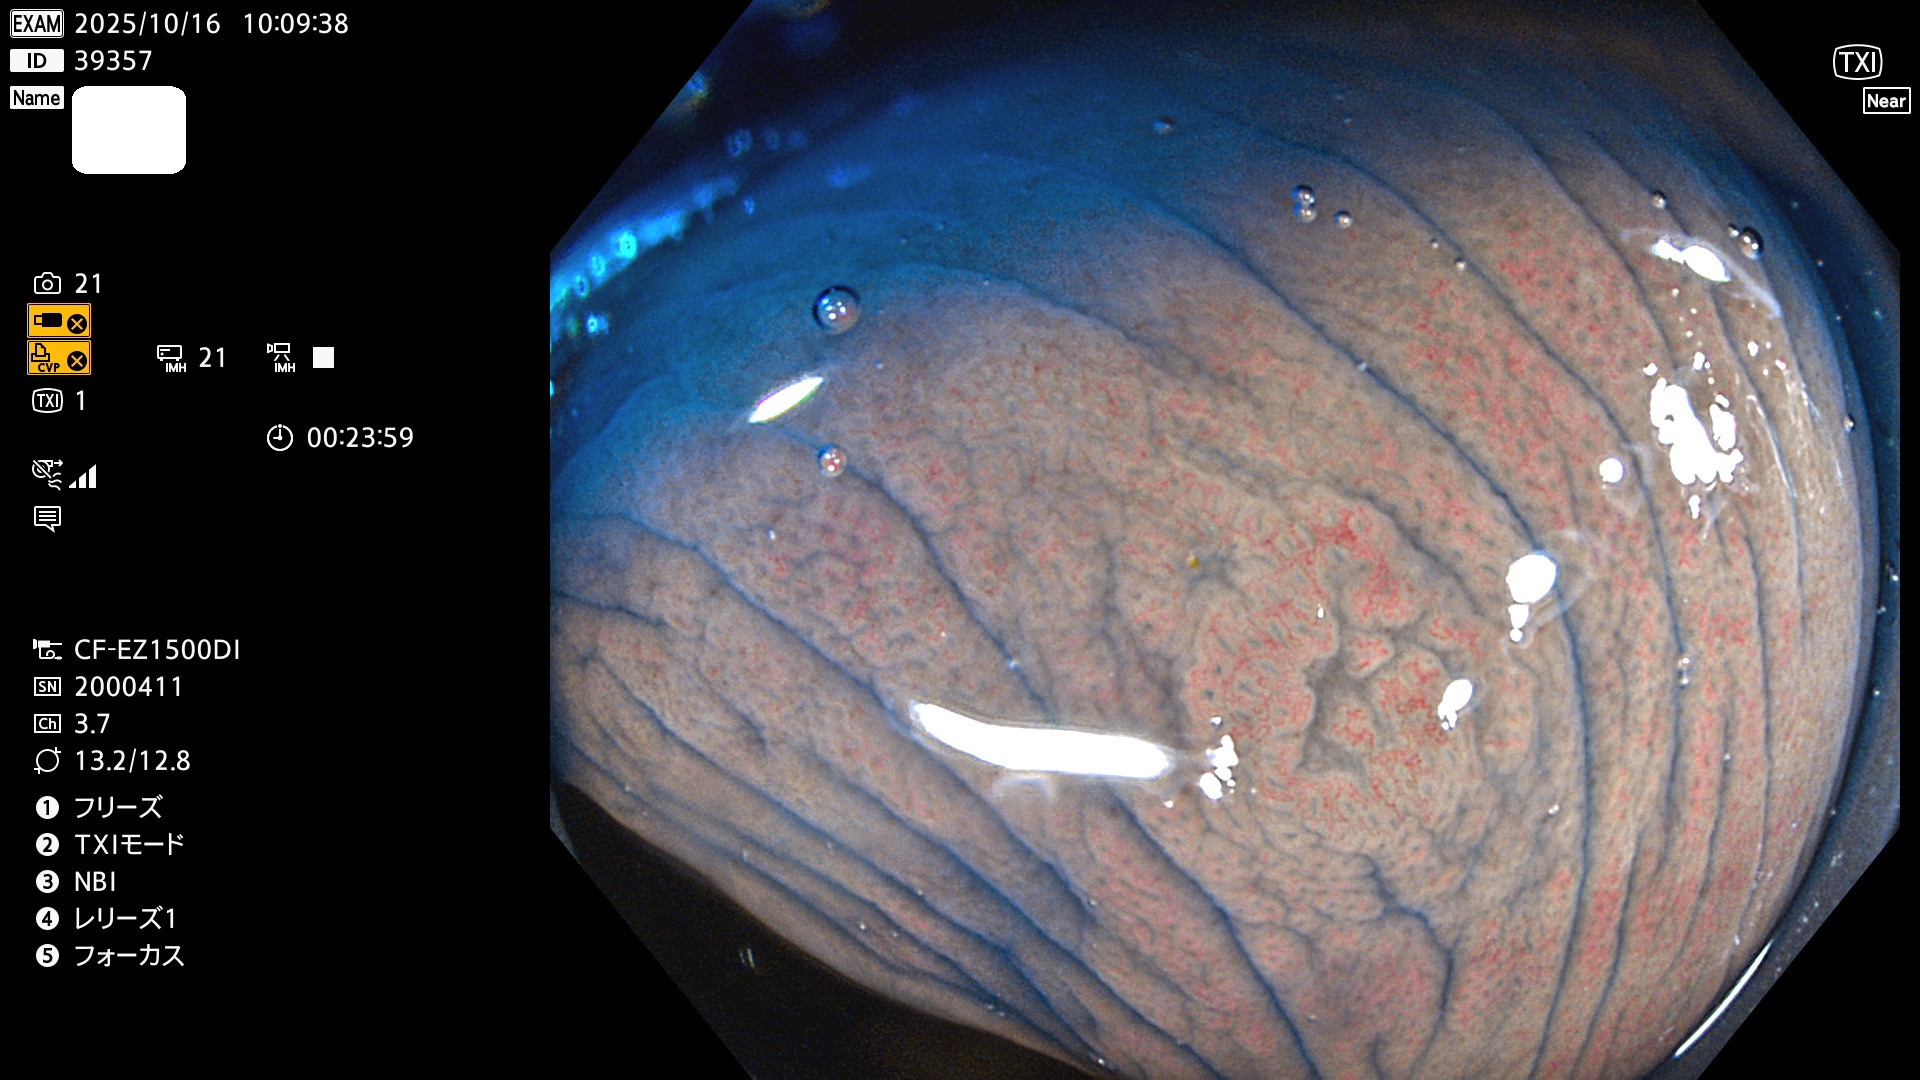

完全に平坦な物をUb、陥凹している物をUcと呼びます。Ubは認識が困難で、Ucはびらん(炎症)と紛らわしいために見落とされやすく、「内視鏡後・大腸癌」の原因になります。

専門的)Uc=De Novo癌? 内視鏡の解像度が低かった時代、このような説もありました。しかし今日の高精度内視鏡では良性の微小なUc型腺腫(APC遺伝子異常の腺腫)が日常的に見つかります。Ucこそが多段階発癌(Adenoma-Carcinoma Sequence)のMain Routeです。

毎週の検査(木・金・土・日)に発見されたUbとUc型・腺腫を、その週の日曜の夜にUPし1週間、提示します。

2025年10月16日〜10月19日の4日間(40件)2個 (Uc_ADR=2個/40人=5%)